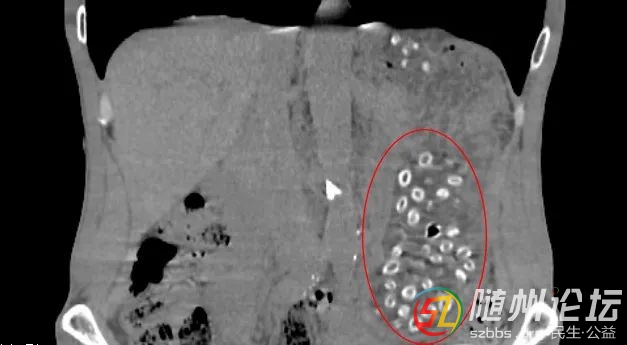

經(jīng)CT檢查后發(fā)現(xiàn)胃潴留,胃內(nèi)可見大量顆粒狀物體,密密麻麻,詢問得知王大伯近期大量食用楊梅且不吐核,以下影像中呈現(xiàn)的就是沒有消化的楊梅核。